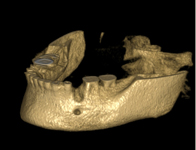

Augmentační postupy jsou zákroky minimálně invazivní až po náročnější operace upravující nedostatečnou nabídku alveolární kosti co do kvantity a kvality.

Tyto postupy nám umožní doplnit chybějící množství kosti v čelistech pacienta i zlepšit kvalitu kosti. Většinou se setkáváme s omezenou nabídkou kostní tkáně díky resorpčním (úbytkovým) procesům způsobených věkem či vytržením zubu, přítomností anatomických struktur jako je čelistní dutina, nervový kanál nebo patologických či poúrazových stavů - cysty, zlomeniny.

V těchto případech musíme použít některou z následujících pomocných metod:

použití umělého kostního granulátu

zahušťování kosti a její roztahování pomocí speciálních nástrojů spreading, kondenzace, distrakce

použití vlastí kosti nebo kostních štěpů - Transfer Set BEGO